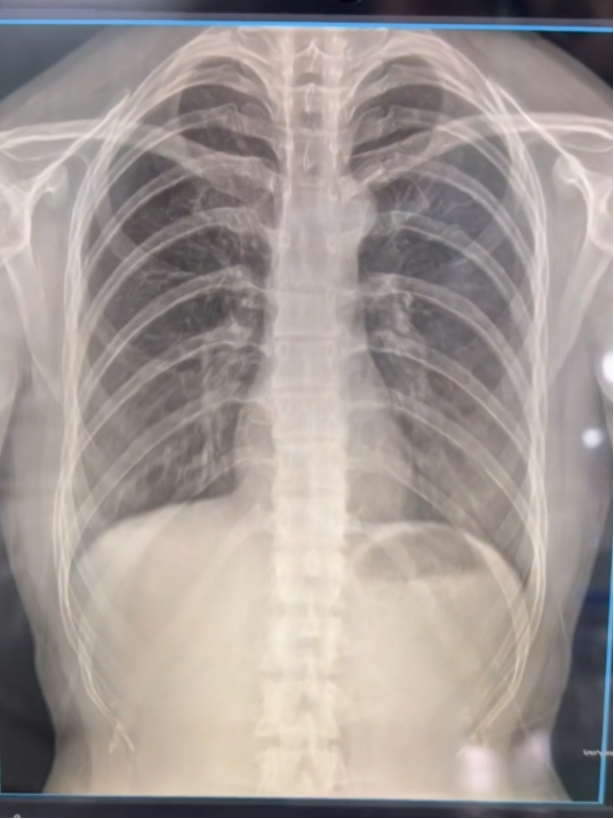

华影光子相机式X射线机(DR)已取得正规医疗器械注册证,突破市面同类产品仅能做四肢检查的局限,具备专业人体胸片拍摄资质,可完成临床数字化X射线摄影诊断,精准匹配国家公卫老年人体检胸片筛查要求,为基层肺结核、肺部肿瘤等疾病早筛提供专业影像支持。

贴合基层体检季任务重、老年人耐受时间短的痛点,设备实现3秒快速成像,搭配10秒AI智能初筛,大幅缩短老年人等候时间,提升胸片筛查效率,轻松应对集中体检的高强度工作,让公卫体检服务更高效、更贴心。